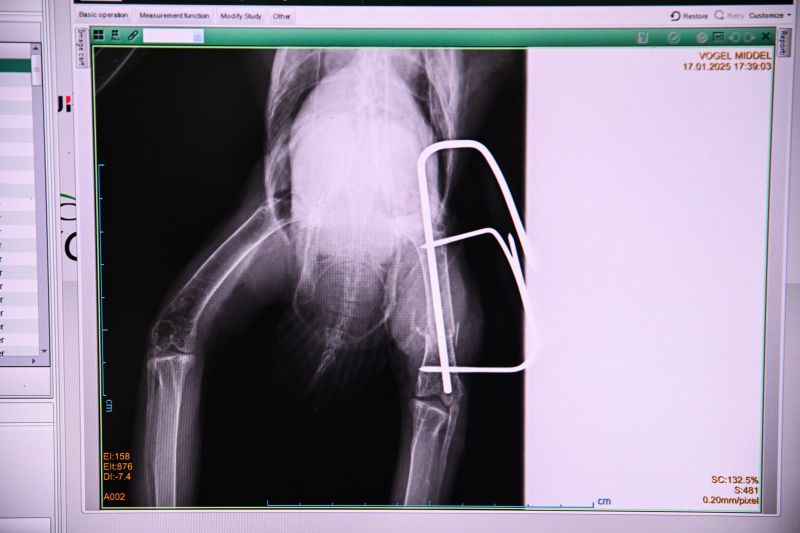

Uilen met gebroken vleugels, dassen die slachtoffer werden van het verkeer, buizerds die verstrikt raakten in prikkeldraad,... In het Natuurhulpcentrum worden almaar meer complexe operaties uitgevoerd door ons team van gemotiveerde dierenartsen. Bovendien krijgen we ook vaker te maken met grotere (exotische) dieren zoals leeuwen, tijgers of beren.

De nood aan een professionelere operatiekamer die rekening houdt met de enorme diversiteit aan patiënten die we opvangen, is hoog.